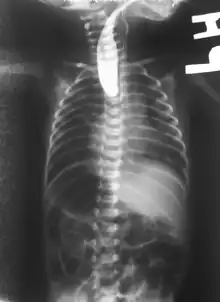

| Common anatomical types of esophageal atresia a) Esophageal atresia with distal tracheoesophageal fistula (86%), Gross C. b) Isolated esophageal atresia without tracheoesophageal fistula (7%), Gross A. c) H-type tracheoesophageal fistula (4%), Gross E.[1] | |

On plain X-ray, a feeding tube will not be seen pass through the esophagus and remain coiled in the upper oesophageal pouch.[8]

If any of the above signs/symptoms are noticed, a catheter is gently passed into the esophagus to check for resistance. If resistance is noted, other studies will be done to confirm the diagnosis. A catheter can be inserted and will show up as white on a regular x-ray film to demonstrate the blind pouch ending. Sometimes a small amount of barium (chalk-like liquid) is placed through the mouth to diagnose the problems. However, performing such an oral contrast study is not advised due to a risk of aspiration.[27]